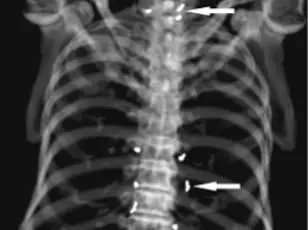

The discovery came during a routine imaging scan to assess the progression of her osteoarthritis.

Instead of revealing the expected signs of joint degeneration, the X-ray exposed a dense cluster of metallic specks surrounding her kneecap and extending into her shin bone and upper thigh.

These specks, later confirmed to be the gold threads, were not only obstructing the view of critical anatomical structures but also potentially interfering with the body’s natural healing processes.

By 2022, the medical community had documented even more alarming cases.

A 73-year-old Korean man was hospitalized for a stroke.

During his evaluation, he described a 30-year history of widespread joint pain he had self-treated with gold thread acupuncture.

X-rays revealed thousands of the embedded threads throughout his body.

This revelation underscored the potential for long-term complications when such procedures are performed without medical oversight or follow-up.